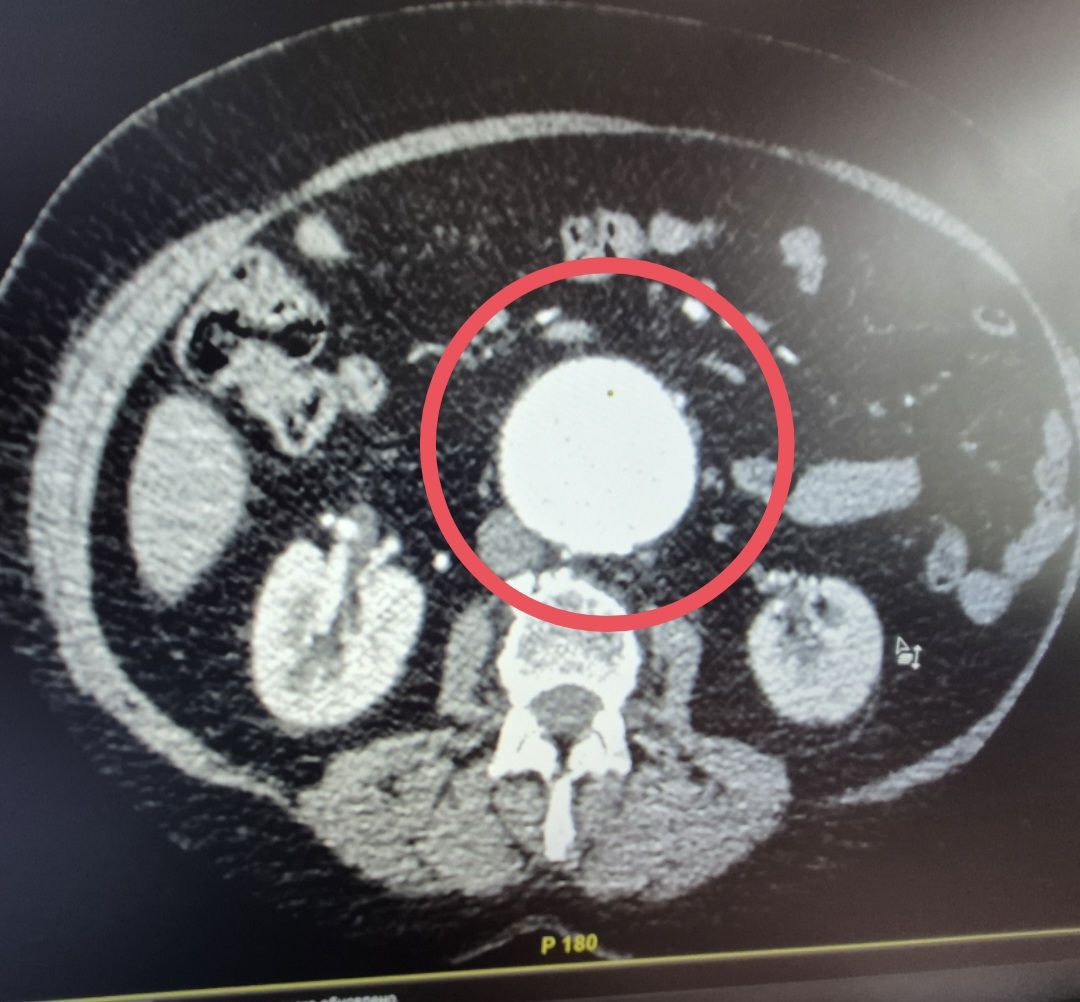

Балаковские хирурги прооперировали женщину с "бомбой замедленного действия"

В Балаковскую городскую больницу поступила 60-летняя женщина с сложным диагнозом - мешотчатой аневризмой брюшной аорты. Аневризма брюшной аорты считается "бомбой замедленного действия", а мешотчатая форма особенно опасна из-за риска мгновенного разрыва.

За лечение пациентки взялся заведующий отделением сосудистой хирургии Балаковской больницы. Операция длилась более шести часов и прошла успешно.